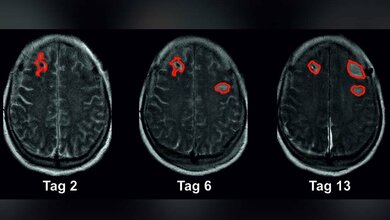

Als zeitsparende Unterstützung sind mittlerweile computergestützte Analyseprogramme auf dem Markt. Dazu wird ein lernender Algorithmus anhand möglichst vieler CT-Bilddaten trainiert, Gefäßverschlüsse jeder Lage und Ausprägung im Gehirn möglichst sicher zu erkennen. Das Problem bei kommerziellen Anbietern: Sie haben nur eingeschränkten Zugang zu klinischen Daten, das Trainingsmaterial der Künstlichen Intelligenz (KI) ist daher nicht immer repräsentativ und die verwendete Methodik entspricht nicht immer dem aktuellen Stand der Wissenschaft. In Folge erkennt die KI vor allem Verschlüsse in seltener betroffenen Hirngefäßen schlecht.

Heidelberger Algorithmus deutlich genauer

Anders beim Heidelberger Analysetool: Der Algorithmus wurde mit Bilddaten von mehr als 1.000 Patientinnen und -Patienten, die mit Verdacht auf Schlaganfall am UKHD untersucht und behandelt wurden, entwickelt. Anschließend bewährte er sich in einer sechsmonatigen Testphase an drei ausgewählten Partnerkliniken des Schlaganfallkonsortiums Rhein-Neckar (FAST) und am UKB. „Unser Algorithmus zeigte sich im Vergleich zu kommerziellen KI-Produkten deutlich genauer. Darüber hinaus ist der negative Vorhersagewert, also dass bei Ausschluss eines Gefäßverschlusses durch den Algorithmus die Vorhersage tatsächlich korrekt ist, mit bis zu 97 Prozent schon sehr gut", so Vollmuth. „Unser Ziel ist es aber, den Algorithmus noch besser zu machen."